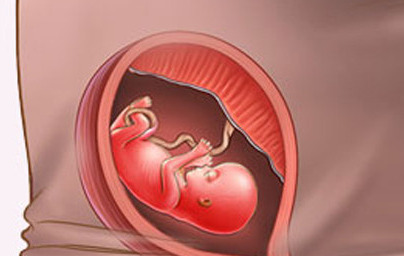

14. teden nosečnosti

Telo v rasti počasi pričenja dohitevati glavo. Če je plod deklica, ima zdaj v jajčnikih več kot 2 milijona jajčec. Spoznajte 13. teden nosečnosti in si preberite celoten opis...

Kaj se dogaja v 13. tednu?

V 13. tednu na drobcenih prstkih vašega ploda pričnejo nastajati prstni odtisi. Žile in organi ploda so jasno vidni skozi zelo tanko kožo, telo pa v rasti počasi pričenja dohitevati glavo. Če je plod deklica, ima zdaj v jajčnikih več kot 2 milijona jajčec.